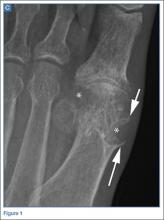

The radiographs of the right foot excluded fracture as the underlying etiology of the patient’s pain. The findings included soft tissue swelling and periarticular (ie, near but not involving the joint) erosions involving the first metatarsal head (white asterisks, Figure 1c). The erosion on the medial aspect of the metatarsal head had remodeling of bone at the periphery of the erosion, which created the appearance of “overhanging edges” (white arrows, Figure 1c). The radiographic appearance suggests the diagnosis of gouty arthritis.

Regarding imaging studies, radiography is often the first imaging test performed to evaluate for gout, and can reveal characteristic findings such as periarticular erosions with sclerotic margins, overhanging edges of remodeling bone, and adjacent soft tissue tophi. These findings, however, occur late in the disease. Ultrasound may be useful for earlier diagnosis with the “double contour sign,” which is a specific finding representing the appearance of urate crystals deposited on the hyaline cartilage of the joint. Dual-energy computed tomography (CT) has been shown to not only demonstrate early erosions and soft tissue tophi, but also to characterize the crystals, making CT a highly sensitive and specific test for the detection of gouty arthritis.4